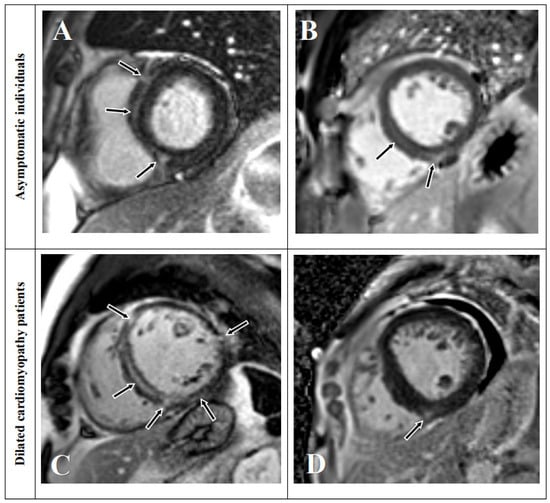

3.2. LGE Characteristics

3.3. Overlap Percentage of LGE Extent

3.6. LGE Distribution